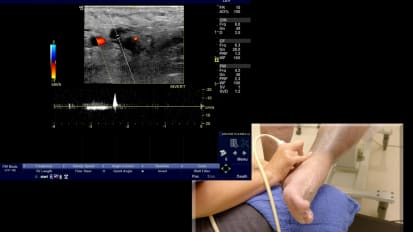

Chapters Transcript Video Left Refluxing Perforating Vein Ablation with Venclose Maven™ Perforator Catheter Featuring: Dr. Jeffrey Carr; Duration: 13 minutes A 46 year old man who has had a very long standing chronic disease of very very strong family history. And he came to me uh complaining of years and years of heaviness, aching, tired, fatigue in his legs, the throbbing and restless legs and cramping. And not to mention, he had over 12 episodes of recurrent thrombophlebitis in both legs. The left leg was worse than the others uh than the right. Um He underwent laser ablation therapy 15 years ago by another provider just of the thigh portion of the great sinus vein, but really did not achieve really any significant improvement over the ensuing years. On his initial duplex ultrasound, we showed closure of that thigh portion of the great sinus vein, but pathologic reflux of bilateral great sap anus and small sinus veins as well as a very large left distal calf perforator of 5.8 centime millimeters and 1942 milliseconds of reflux. Now, he had focal pain over the site of this distal calf perforator that persists despite treatment of his left great sinus vein. And so that's the focus of our intervention today. Uh In addition, because of his recurrent thrombophlebitis is at high risk uh for additional episodes, they've been very painful. Um And he has many superficial vars as well. Uh, that had drained into the superficial system that we will plan on tackling later with phlebectomy. We wanna look at our treatment length that we think we can adopt from that distal end. Yeah, you come, come back, do five. Ok. Just stay right there. That's good. That's good. Ok. So that's do not cross mark that, that's our, that's our safety distance. And now we're gonna move from there to the entrance. We believe that where we think we're gonna angle in on access right about a little more. OK? So just over 22 centimeters or 20 millimeters, this is a five millimeter coil. It's important not to overdo the lidocaine your wheel. Uh These veins are very vasal reactive. So you gotta be very careful, come up very easy and just put a little wheel there and not too much, just enough so that they don't feel the skin neck again. He has a soft, softer skin. The key is to not to move too much with the sonography and just to find it, you can see the tip. Now, I'm not on the edge of the show me the good lumen, the black lumen. There you go more, a little more. So I'm just about to pierce it. I'm gonna poke, poke through a little bit. No looking real. I think I just grabbed some tissue there. How about now? It feels like it. Anybody see. Ok, I am in the vessel. I'm gonna hold really still. I like my assistant to put that in because I'm focusing on not moving an iota and now you say I landed the plane, not at the beginning of the runway, but you know, maybe 1/4 of the way and in Korea just put the wire down and it made it to the edge and it actually made the turn. So it's a looped. It's a little loop. No, it's not loop. It's perfect. It's in the PT. So I'm in the vessel. I'm gonna take my wire out, gonna make a little incision, not my wire, my needle out and then I'm gonna keep that wire right there. We don't wanna lose that position because we, we're pretty pleased that it went in where we hoped I'm gonna make a little skin nick because I don't want resistance when we put the sheath in to pull my wire out. So just a little 11 blade skin nick. And then can you load the space so she'll load this on. I'm just really focusing on not moving that wire and then notice the dilator the distance of the dialer to the sheath. Ok? Because the key is to get the sheet in the dialer is gonna go into that vein, but we're gonna make sure the sheath does. So I'm holding my wire, Casey's gonna show me approaching it. Ok. So we have the dilator in the vein, we have the wire around into the poster tubule. But you can see it's very challenging to know where the sheath begins. And then what's where the sheath and the dilator are in relation on the ultrasound. So that's why it was important to look at how much I'm going to anchor the dilator now. Ok. That's a great view. You can see the double density. I'm gonna just try to advance the sheath in over the dilator here without pushing the dilator and, and that's it. So now my sheet is in and I'm pulling the dilator out and we have that wire in a good position. So I think we can pull everything out, right? We're going to OK. And then we have feedback that we're in the lumen. Wonderful little flesh, please. I'm gonna jiggle just a little. So here I am to the right. I'm not even in it yet. I gotta shallow. My angle of it. Oh, there it is. Right. OK. We're coming into the top into that tributary. Now, you can see the truck, the needle, but I'm off plane. So she's gonna open up the lu in there. I'm not moving right there. I wanna see, I'm gonna aim for her target right there. So I moved laterally and I think right there, I'm in a good position as I enter in. Can you flush that real quick. Just a light little flush. We're going to just flush that again. That's our feedback. It's very challenging. But I think when we flush, we'll be able to see, um, see the tip of the catheter, just light little flush. Ok. That's good. And you see the bubble, so we know where tip is really at the edge of our right where that turn was. So we're in really good position. I'd rather be too far forward than not in the vein. So now we're inserting the maven which has markings on it and the five millimeter tip, I'm anchoring this very firm not to pull back. And I'm really just wanna come in with the maven. You can see it coming in now and I'm gonna go right to that edge and I think that's right where we initially preplanned pretty close. I'm gonna pull back now with the sheath, I'm gonna remove the sheath completely. Very careful not to let the maven come back. It's very lubricious, slippery and it can easily come out if you're not anchoring it. Yeah. So make sure you got dry hands and catheter that we're in good position. I like to note on the skin where we are, you have a number there four on the skin. So it's about, it's just under four and now we're gonna check our distal tip just like we did on the pre and we're gonna try to locate the coil and I could see this many wants to come and point to it, please. So the tip, the plastic tip is right at the junction. Correct, right down there. It's very hard to see it, but it's right there. And 3.5 millimeters from there to, to the coil is the beginning of the coil. So it looks like the coil starts right there. Go ahead and measure that. And that's confirmatory. Yeah. 3.5. We're perfect. So we're very confident that dense white is the beginning is the five millimeter coil. Can you measure the coil itself just to show that we're all on the same page. This is so important to take your time and make sure you know exactly what it is because so I'm gonna put it in there. I'm gonna show I'm pushing it in just to show the coil five millimeter coil. There it is OK. So take that off. So a little pinch here, fill some burn. So you can see my needles perfect. It's going right to the tip and I'm pushing the posterior tibial vein away from my treatment location. Again, I'm gonna pull back before I heat here. I'm a little distal and again, I'm kinda going on all sides of this thing. I'm gonna come back a little bit a lot more just to get this point here. We also want to stay away from the skin is another hazard, five millimeters or greater. Here we go first treatment. So we're getting feedback from the generator. But at the same time, it's important to look at the ultrasound and see if you're getting treatment affect where you think, where you believed it was occurring. So we're exactly where we hoped and thought you could see the e echo density occurring. Often. You'll see a little scintillating or bubbling, boiling of the blood. And this is our second treatment cycle. 22nd cycles. Target is about 100 and 30 °C. You don't feel anything, not a thing. He's enjoying the ride and we're starting to see some echo density, meaning we have treatment effect. We're getting coagulum, we're denuding the endothelium of the vein to destroy it on and create inflammation. So I'm very pleased with this location at the deep and we're well enough away from the posterior tibial vein there. From experience to date. We have, we've been able to inform ourselves about this. We early on in the original study. Um the ID E trial, we worked from one treatment per location to six. We found safety at either one of those uh strategies, but we saw a few pas early on when it was just a one and done uh location. Um I think there are a lot of variables that go into it. Um I believe if you're in the lumen and are absolutely certain, you know, you're gonna deliver the therapy. But uh we've been practicing and recommending up front the six So I'm gonna stop here. We did six. We're gonna recommend six per location up front to get clo the best chance for closure. So I'm gonna be staring down here to pull back five and my and Casey's gonna be looking to see if it matches up what we think on the screen. So here I go, I'm pulling back and that's in the middle of the next one. So we think that's five. You agree? Yeah, there could be, there could, there could be plaques. I'm sorry, there could be slack stored in the catheter. You may not be pulling back. Exactly five. So just kind of be aware of that. You see the poster tibial head flow and you see that's the closed perforator there, you can see it to the top left here where it drained in and we see complete closure uh from the, from the treatments today. And then now I just show the posterior tibial really try to line that out and we have flow. There you go. Now we're really laying it out and it's hard when there's compressed images. So uh do your best. Uh the best is to follow up with these patients. Published December 13, 2024 Created by Related Presenters Jeffrey Carr, MD, FACC, FSCAI Interventional Cardiology, Cardiovascular Disease, Internal MedicineCHRISTUS Trinity Clinic View full profile